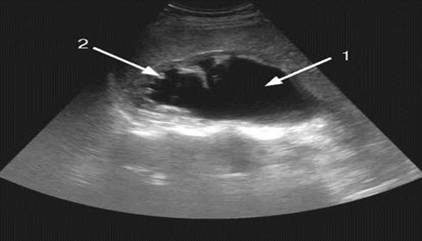

Сонограма. Гідронефроз: 1 - виражене розширення балії і чашок із згладжуванням їх контурів; 2 - різке стоншення паренхіми нирки